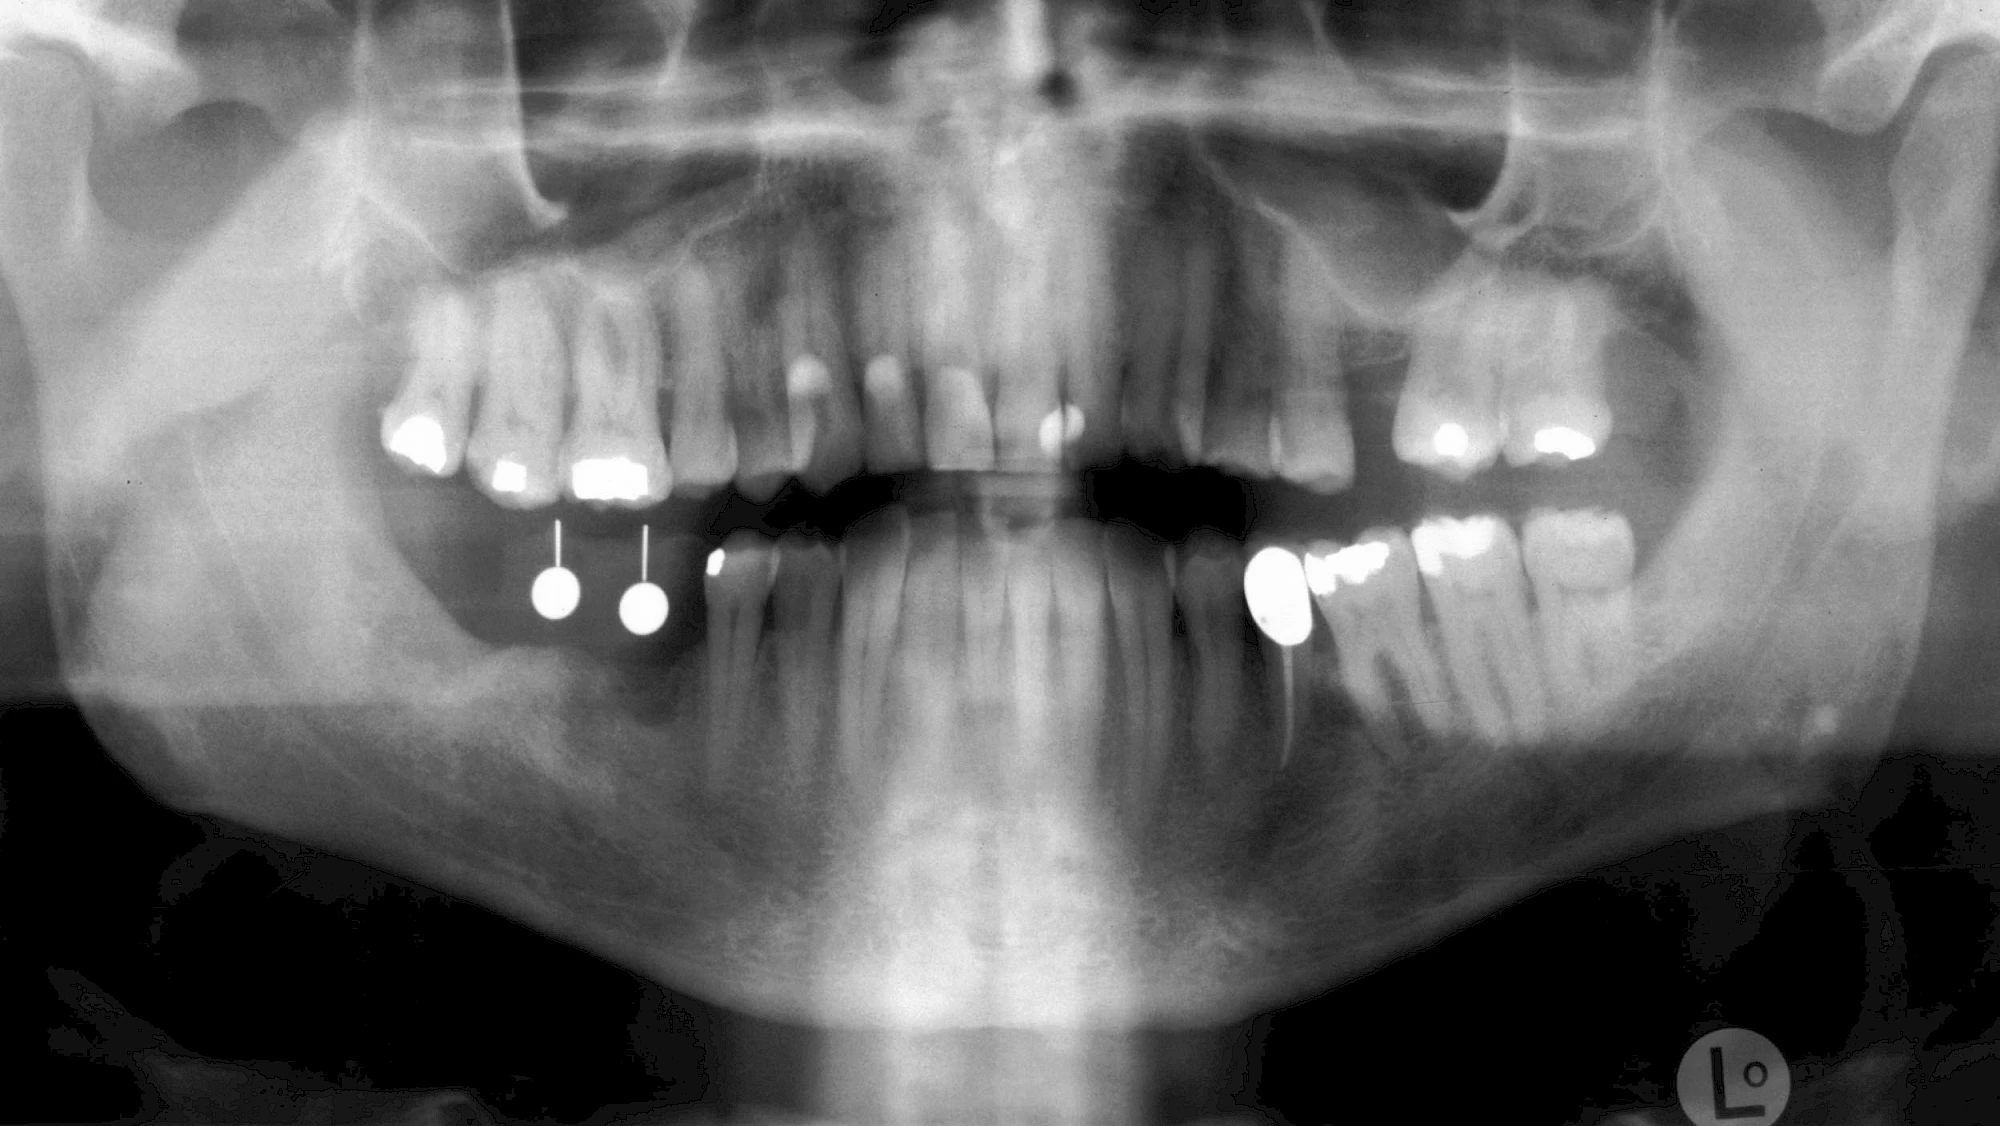

Damit Implantate an der richtigen Stelle im Kieferknochen platziert werden könen, gibt es heute vielfältige Möglichkeiten der Planung. In vielen Situationen kann die Erfahrung des Zahnarztes ausreichend sein.

Nicht selten ist jedoch auch eine technisch aufwändigere Vermessung im Vorfeld sinnvoll, z. B.:

- Wenn sich der Kieferknochen abgebaut hat

- Wenn der Nervverlauf im Unterkiefer beachtet werden muss

- Wenn die Ausdehung der Kieferhöhle im Oberkiefer beachtet werden muss

- Wenn wenige Restzähne keine gute Orientierung erlauben

In diesen Fällen kann die Planung mittels verschieden aufwendiger Röntgen-Techniken (Übersichtsaufnahme, DVT) ggf. unter Zuhilfenahme speziell angefertigter Planungsschablonen sinnvoll sein.